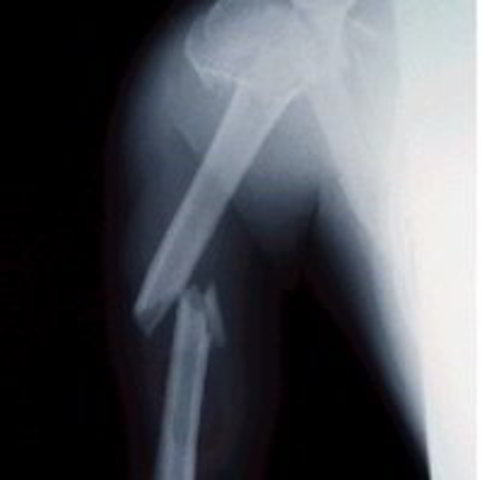

• fractura de antebrazo

fractura de antebrazo

se fractura el antebrazo cuando el padre llegaba del trabajo